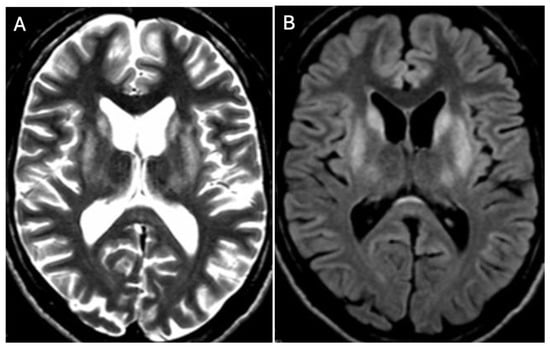

- Favrole, P.; Chabriat, H.; Guichard, J.P.; Woimant, F. Clinical correlates of cerebral water diffusion in Wilson disease. Neurology 2006, 66, 384–389. [Google Scholar] [CrossRef] [PubMed]

- Sener, R.N. Diffusion MRI findings in Wilson’s disease. Comput. Med. Imaging Graph. 2003, 27, 17–21. [Google Scholar] [CrossRef] [PubMed]

- Yu, X.E.; Gao, S.; Yang, R.M.; Han, Y.Z. MR imaging of the brain in neurologic Wilson disease. AJNR Am. J. Neuroradiol. 2019, 40, 178–183. [Google Scholar] [CrossRef] [PubMed]